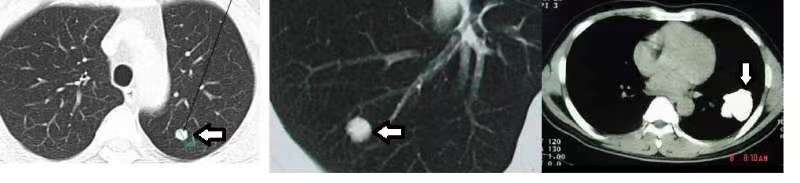

钙化结节:钙化灶影像上表现为密度很高(与骨头密度相当)、均匀一致的白色结节。一些炎症、结核、寄生虫疾病,当原有肺组织被破坏,免疫系统对“侵略者”进行吞噬、包裹,最终导致钙盐沉积在这些坏死组织形成一个坚硬的“石头子儿”样的结节,就变成了影像中的钙化灶。均匀一致的钙化结节是完全不需要您担忧的,因为那就是一块肺里面的小石子儿。

实性结节:指的是整个结节密度较一致且明显大于周围正常肺组织,成分较实(但没达到钙化程度)的结节。一般情况下这种结节所含的细胞组织成分较多,边界往往比较清晰。小于5mm的一般定期复查就好,而超过8mm的就需要专业医生来判断其良恶性。

磨玻璃结节:肺磨玻璃结节(GGO,ground glass opacity)在胸部CT表现为密度轻度增高的云雾状淡薄影 / 圆形结节,密度像磨砂玻璃或者云朵的一样,所以称之为磨玻璃结节。一般分为纯磨玻璃结节和部分实性磨玻璃结节。如果磨玻璃结节被描述为“边界清楚”且大于8mm时,那就需要高度警惕了,因为其中70%以上都是恶性的。而参杂部分实性成分的磨玻璃结节更是高达90%为恶性结节!